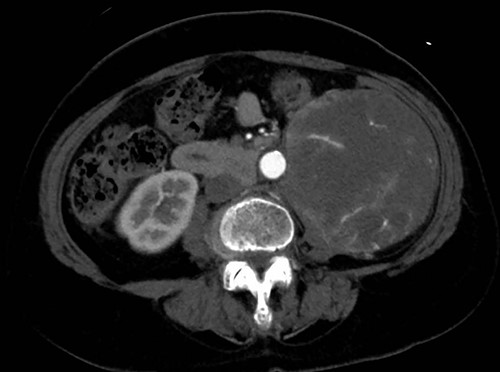

A 76-year-old woman with a giant retroperitoneal tumor was scheduled for surgical resection (Fig. 1). However, preoperative examination revealed severe aortic valve stenosis (AS); therefore, the patient first underwent minimally invasive aortic valve replacement (MICS-AVR) for severe AS. In this operation, we approached the surgical site through the right third intercostal space, and cardiopulmonary bypass was established with right femoral arterial and venous cannulation. PERCEVAL (Livanova, London, UK), a sutureless valve, was used as the artificial valve. Five days post-operatively, she complained of back pain, and a computed tomography (CT) scan revealed bleeding in the tumor and tumor growth. There were no findings of aortic dissection. A peripheral branch of the left third lumbar artery seemed to be the bleeding site; thus, lumbar artery transcatheter artery embolism (TAE) was performed. Although the bleeding stopped, early surgery was considered to be appropriate for the tumor. Therefore, retroperitoneal tumor resection and left nephrectomy were performed on the 12th post-operative day. Four days after tumor resection, the patient suddenly experienced persistent back pain again. CT revealed a Type B AAD. The aorta was dissected from the distal part of the left subclavian artery (LSA) to the level of the right renal artery, and an ulcer-like projection (ULP) was observed at the distal arch (Fig. 2). Although conservative treatment was started immediately, her back pain persisted and follow-up CT revealed slight growth of the ULP. Thus, we decided to perform thoracic endovascular aortic repair (TEVAR) using Valiant (Medtronic, Minneapolis, USA). Before the TEVAR procedure, we performed extra-anatomical bypass from the left common carotid artery to the LSA using PROPATEN (Gore, USA). The Valiant was deployed from Zone2 to just above the celiac artery (Fig. 3). The post-operative course was uneventful, and the patient was discharged without any complications. One year after discharge, CT showed that the aorta was remodeled almost as before (Fig. 4).

Arrow shows false lumen. (a) One week after TEVAR. False lumen still remains. (b) One year after TEVAR. False lumen has almost disappeared.